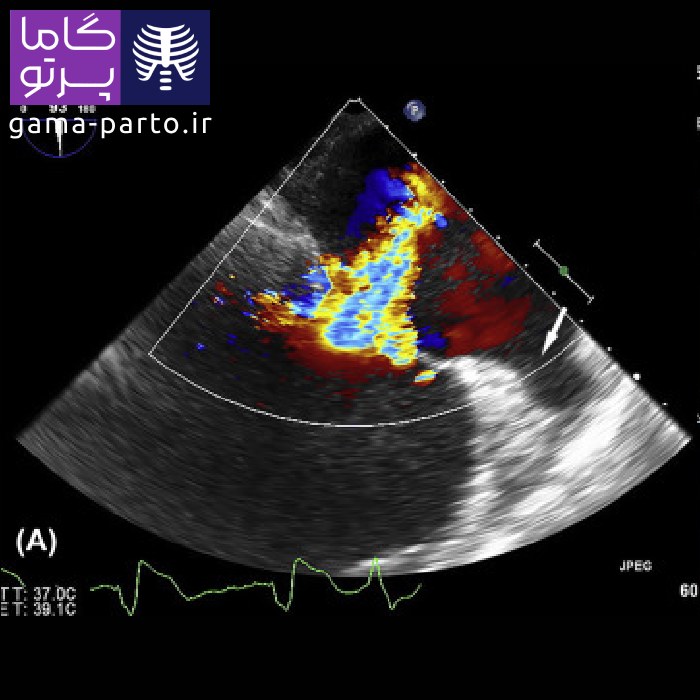

اکو قلب داپلر رنگی - Color Doppler Echocardiography

در تکنیک داپلر رنگی، دادههای مربوط به اندازه و شکل قلب (بهصورت دوبعدی) با اطلاعات داپلر طیفی ترکیب میشوند تا سرعت و جهت جریان خون با رنگهای مختلف نمایش داده شود. بهطور نمونه، رنگ قرمز نشاندهنده حرکت خون به سمت پروب است. این کدگذاری رنگی باعث میشود متخصص قلب بتواند بهسرعت اختلالات احتمالی را شناسایی کند. شایان ذکر است کیفیت تصاویر این روش در دستگاههای قابل حمل گاما پرتو بسیار بالا بوده و برای تشخیص دقیق مورد استفاده قرار میگیرد.